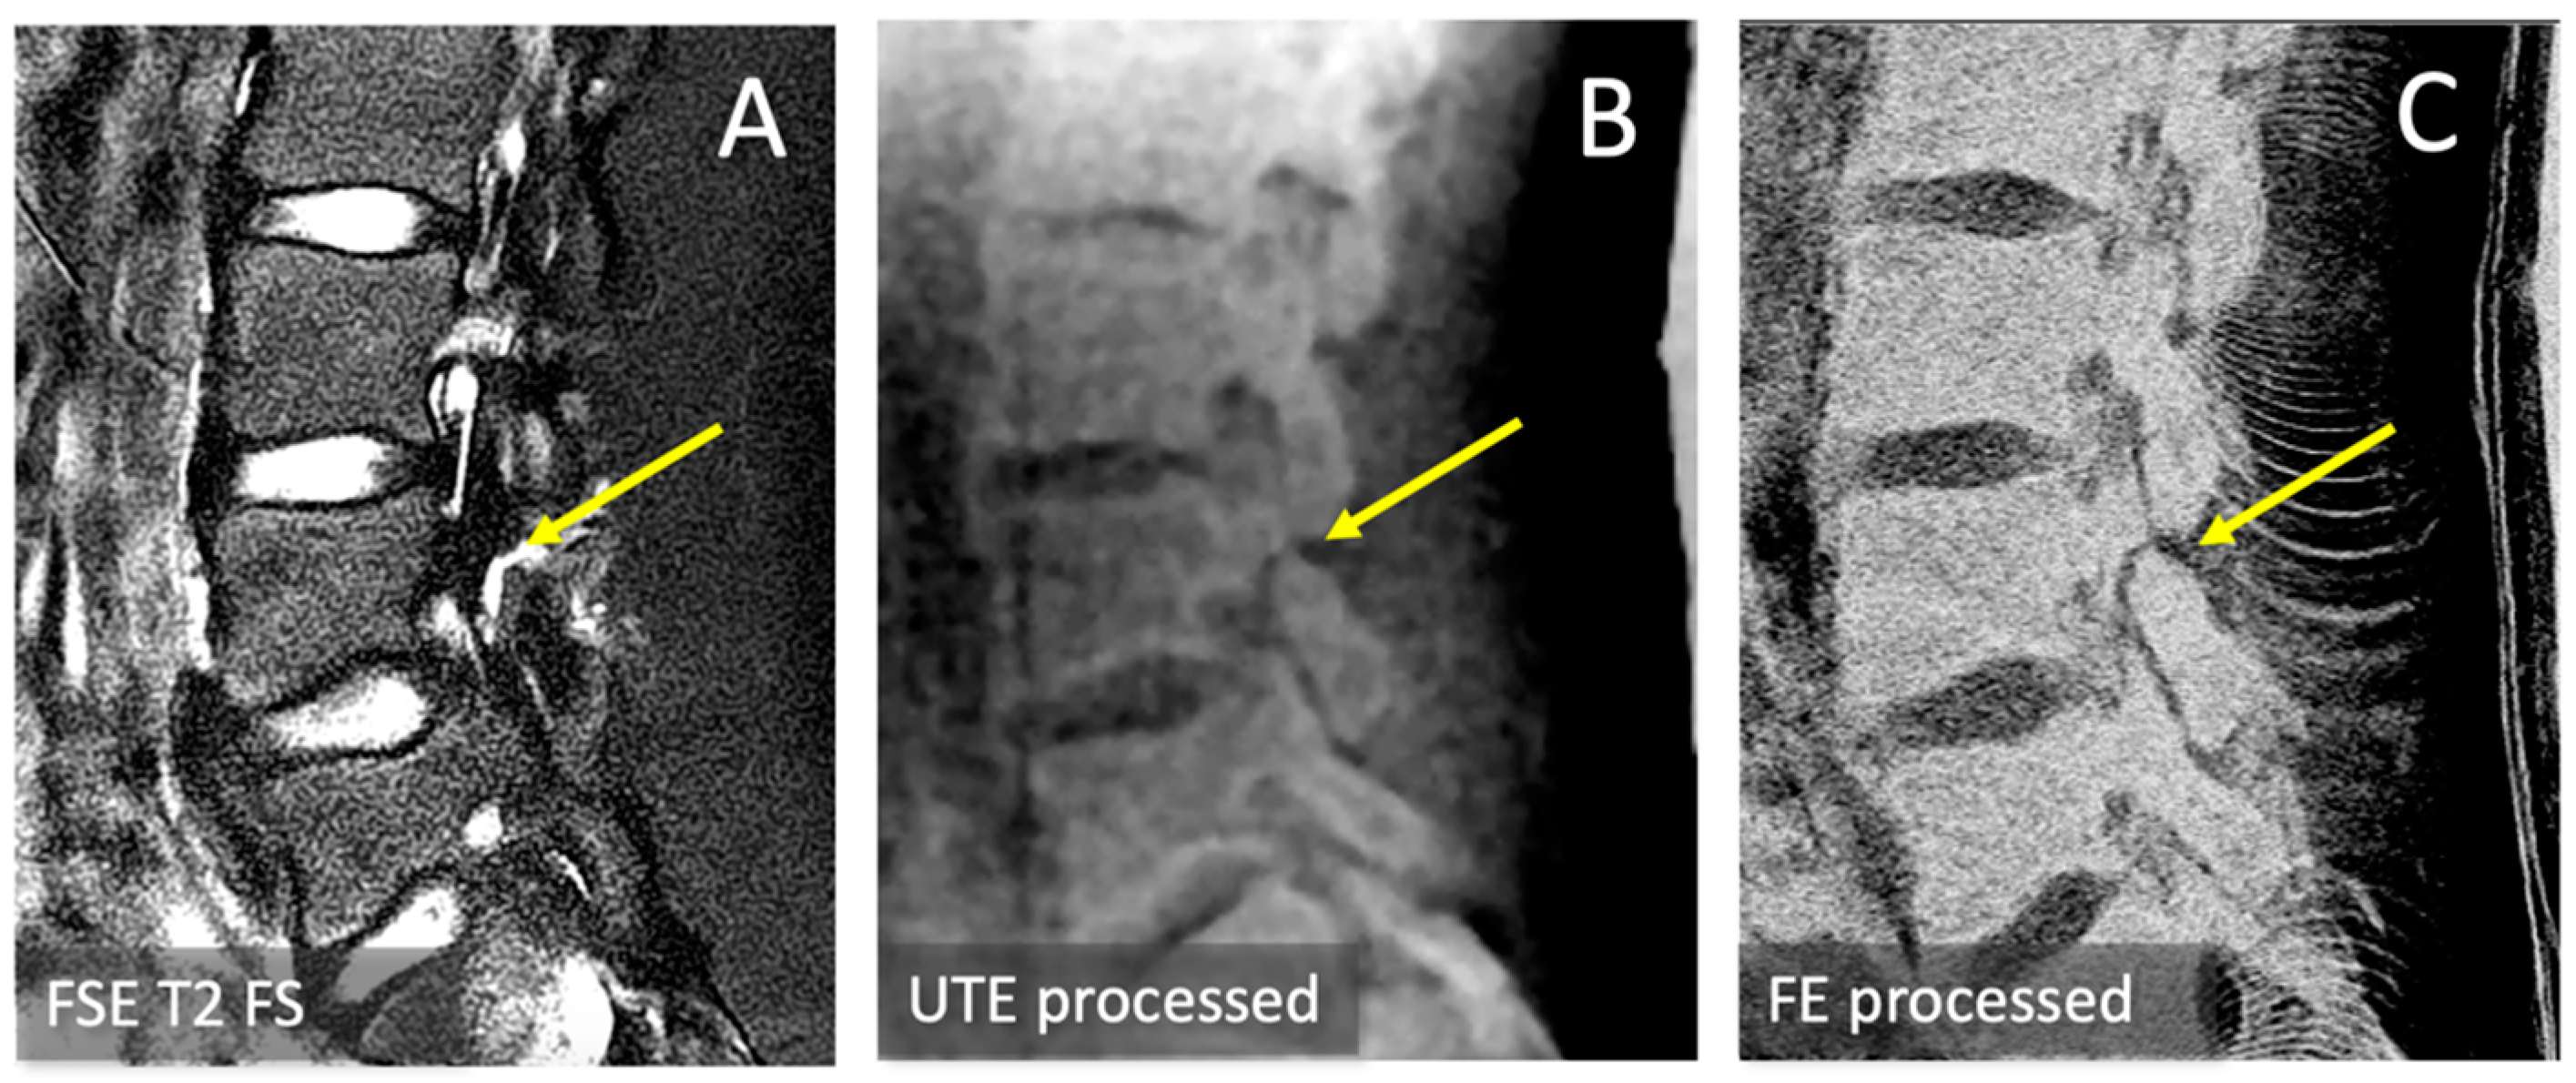

2.6. Spondylolysis Evaluation

3.1. Observations

3.3. Spondylolysis Depiction